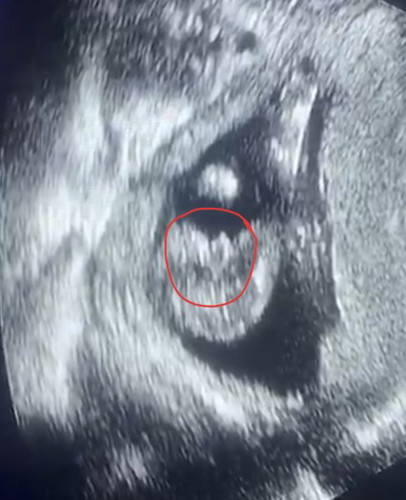

ซาวด์วันนี้ 15 วีค 4 วัน ☺